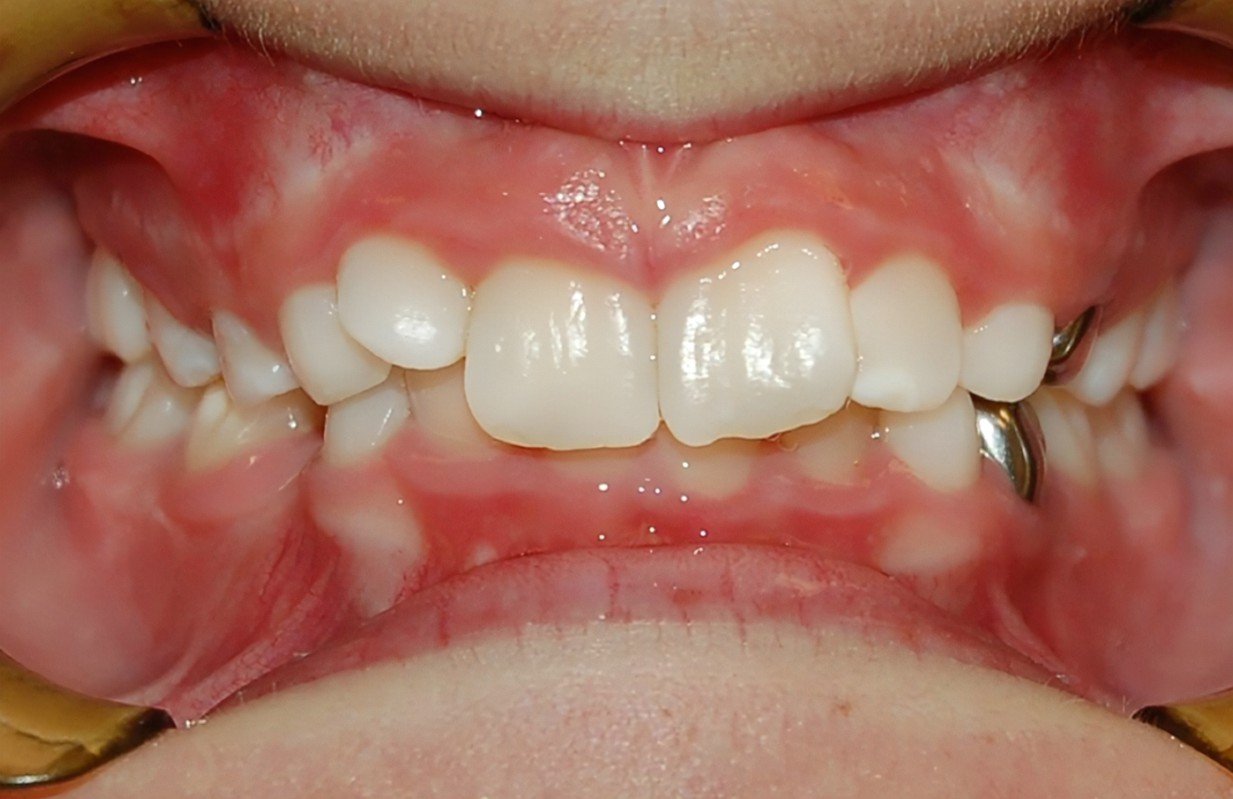

Malocclusion

Clinical Presentation: Misaligned teeth, difficulty chewing, jaw pain, and TMJ discomfort.

Zebris Findings: Abnormal or uneven jaw movements, discrepancies in occlusal contacts, and uneven load distribution across the TMJ.

Anterior Open Bite

Clinical Presentation: Inability of the front teeth to make contact when the back teeth are closed.

Zebris Findings: Anterior segment showing no contact during occlusion, leading to compensatory movements in the jaw and TMJ strain.

Deep Bite (Overbite)

Clinical Presentation: Excessive overlap of the front teeth, jaw pain, and increased wear on the lower front teeth.

Zebris Findings: Increased vertical dimension in the anterior region, excessive loading on the TMJ, and restricted jaw movements.

Crossbite

Clinical Presentation: One or more teeth bite on the inside of the opposing teeth.

Zebris Findings: Lateral discrepancies in jaw movement, uneven load distribution, and compensatory asymmetrical movements.